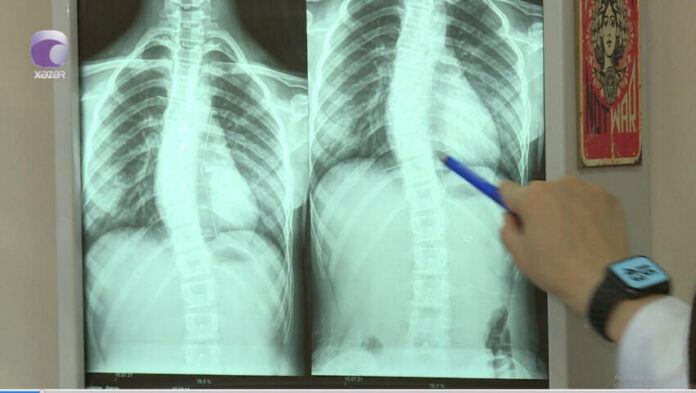

“Son zamanlar 8-12 yaş aralığındakı uşaqlarda bel və boyun ağrıları ilə bağlı şikayətlər nəzərəçarpacaq dərəcədə artıb.

Halbuki, illər öncə uşaqlarda belə problemlər olmurdu. Bunu fizioterapevt Səidə Kərimova “Xəzər xəbər”ə müsahibəsində deyib.

Həkim səbəb olaraq bildirdi ki, uşaqların çantaları kifayət qədər ağırdır. Çiyin ağrıları isə xüsusən ona görə yaranır ki, ağır çantaları daşıyarkən, kəmərləri uşağın yumşaq toxumasını sıxıb kəsir.

Həkim bildirdi ki, bu yaşda uşaqlar oturanda, xüsusilə də dərs oxuyarkən, qamətini dik tutmalıdır.